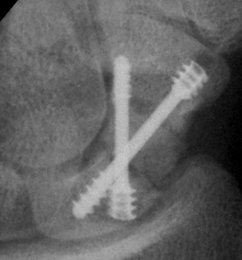

Case 4. Nonunion with a graft and screws placed in both directions from a single palmar approach, hyperextending the wrist for the proximal entry...

Click for larger image

and with the graft:

and with consolidation,